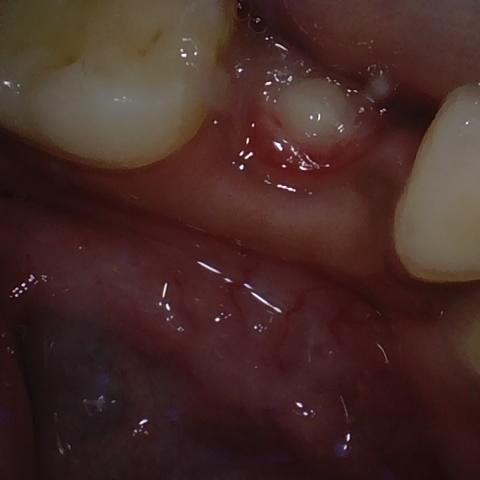

Annotated as "Good"